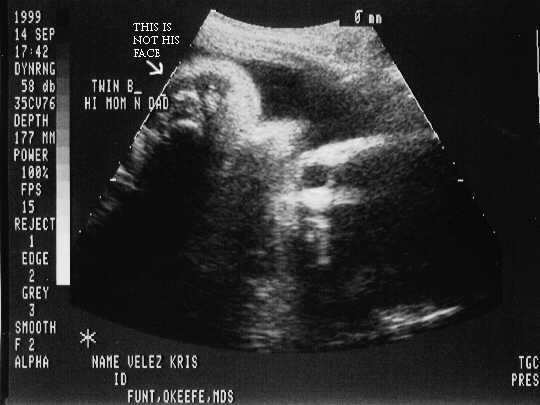

September 14, 1999 Sonograms

Kris is in her 35th week. She can go in labor anytime now!

Kristofer Henry weighs 5.1 pounds.

Kristofer Henry

sono-0914-b-1.JPG - 22.4 K